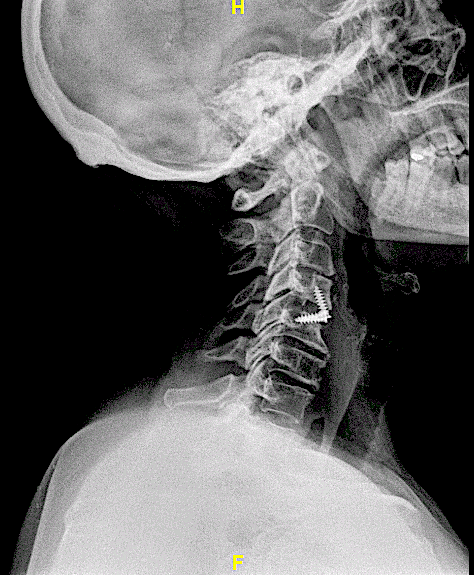

Se realizó un abordaje anterior, con microcirugía, y posterior reconstrucción con caja atornillada